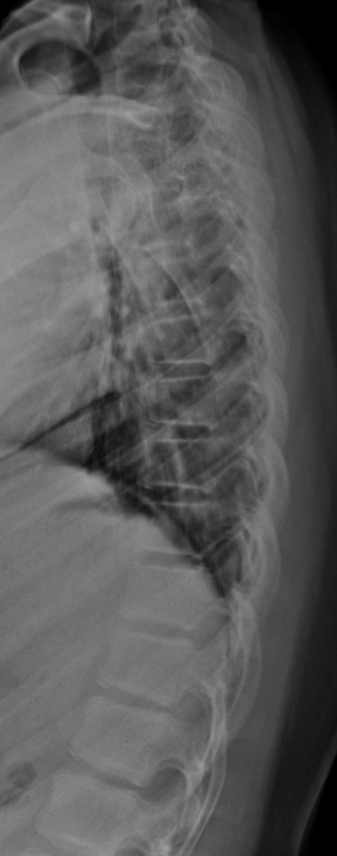

T-spine Lat

- 선 자세(Erect)

- 심장 음영과 척추 겹침을 최소화 하기 위해 몸 왼쪽을 카세트에 붙인다.

- 척추측만(scoliosis) 이 있을 경우, 볼록한 면을 디텍터쪽으로 붙인다.

- 팔을 들어올린다.

- 견갑골 하각(inferior angle of scapula) 에 중심선을 맞춘다.

- 옆으로 누운 자세(Decubitus)

- 심음영과 척추의 겹침을 최소화하기 위해 왼쪽으로 돌려 눕는다.

- 척추측만의 경우 볼록한 면을 디텍터쪽으로 붙인다.

- 베게 혹은 블럭을 머리, 허리, 다리사이에 끼워넣어 척추 정렬을 보상한다.

중심점(CR), 거리(distance)

- 견갑골하각 높이에서 손가락 4개 너비 지점에 수직입사

- 100~150cm

노출조건

- 80KvP / 8mAs

- Grid(+)

- 숨을 참는다.

- 호흡시 장노출(2~3sec)로

이미지